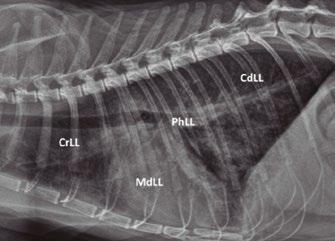

Utilidad clínica de la ecografía pulmonar y cardiaca en urgencias